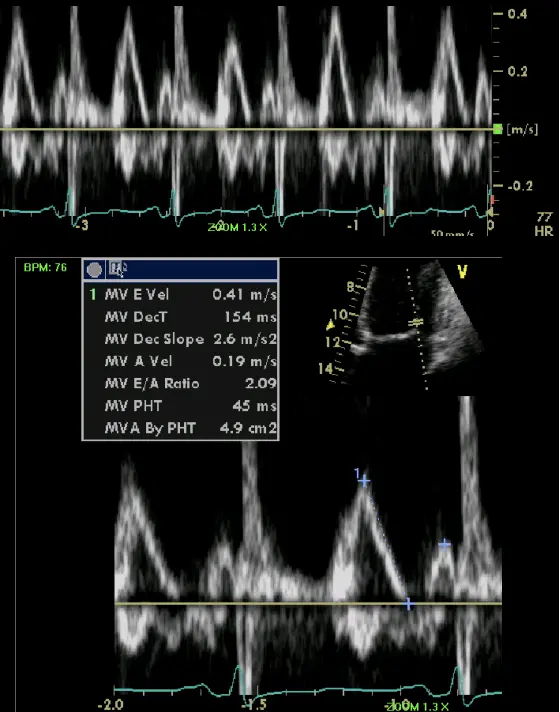

- Specific diagnostic echocardiographic criteria for the diagnosis of constrictive pericarditis has been proposed by the Mayo Clinic and include:

- septal bounce or ventricular septal shift with either medial e′ >8 cm/s or hepatic vein expiratory diastolic reversal ratio >0.78 (sensitivity 87%, specificity 91%; specificity may increase to 97% if all criteria are present with a correspondent decrease of sensitivity to 64%

- Combined parameters from mitral inflow, mitral annular velocities, and hepatic vein velocities have made the diagnosis of constriction and its differentiation from myocardial disease much easier than ever before.3

- Three variables were independently associated with constrictive pericarditis: 1) the presence of ventricular septal shift, 2) medial mitral e’ velocity; and 3) the hepatic vein expiratory diastolic reversal ratio. 2

- The presence of ventricular septal shift in combination with either medial e’ ≥ 9 cm/s or hepatic vein expiratory diastolic reversal ratio ≥ 0.79 (Hepatic vein diastolic reversal velocity / diastolic forward flow velocity) was 87% sensitive and 91% specific for the diagnosis of constrictive pericarditis.

- Mitral inflow ↑ respiratory variation, ↑ E/A, ↓ E deceleration time

- Preserved e’ velocity (septal ≥ lateral)